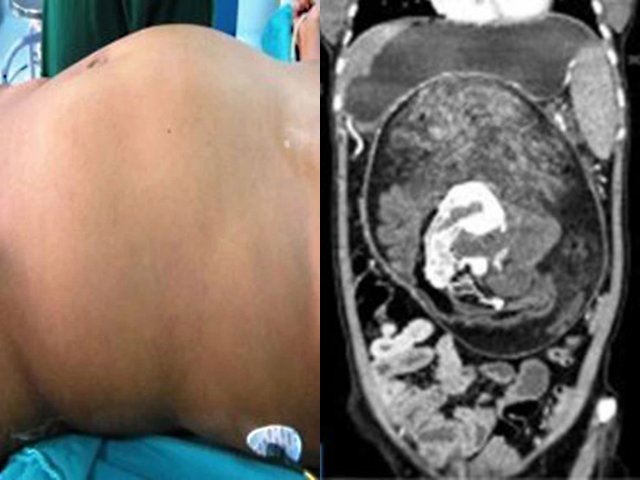

Cô Kavita tới Bệnh viện Acharya Vinoba Bhave trong tình trạng khó thở và đau bụng dữ dội. Nhận thấy tình trạng nghiêm trọng, các bác sĩ đã đưa cô Kavita đi xét nghiệm và phát hiện có một khối u buồng trứng đường kính khổng lồ, lên tới 106 cm. Nếu không được phẫu thuật loại bỏ kịp thời, cô Kavita có thể bị "vỡ bụng" vì khối u bục ra.

Bụng của cô Kavita sưng to bất thường.

Cô Kavita được chẩn đoán mắc u nang huyết thanh, một dạng khối u không phải ung thư, chứa đầy chất lỏng trong suốt. Bác sĩ Arpita Jaiswal Singam, một trong những người điều trị cho cô Kavita cho biết: "Đây là khối u nang lớn nhất mà tôi từng gặp. Nó quá lớn, có đường kính lên tới 106 cm và chiếm 95% chu vi bụng của bệnh nhân".

Bác sĩ loại bỏ thành công khối u nặng 18,1 kg.